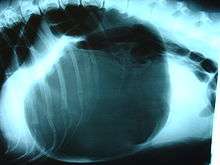

A diagnosis of gastric dilatation-volvulus is made by several factors. The breed and history will often give a significant suspicion of gastric dilatation-volvulus, and the physical exam will often reveal the telltale sign of a distended abdomen with abdominal tympany. Shock is diagnosed by the presence of pale mucous membranes with poor capillary refill, increased heart rate, and poor pulse quality. X-rays (usually taken after decompression of the stomach if the dog is unstable) will show a stomach distended with gas. The pylorus, which normally is ventral and to the right of the body of the stomach, will be cranial to the body of the stomach and left of the midline, often separated on the x-ray by soft tissue and giving the appearance of a separate gas filled pocket (double bubble sign).[17]